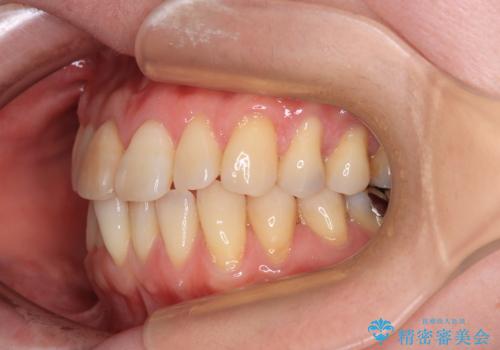

前歯のデコボコをインビザライン・モデレートで矯正治療

- 上下前歯のデコボコを気にして来院された患者様です。

安価なインビザラインパッケージを用いての治療を希望されており、デコボコの程度が中等度であったため、インビザライン・モデレートを用いて矯正治療を行うこととしました。

インビザライン・モデレートは、製作できるアライナーの枚数に制限があるため、移動可能な量に限りがあるものの、インビザライン・ライトよりも枚数が多いため、幅広い症例に対応可能です。